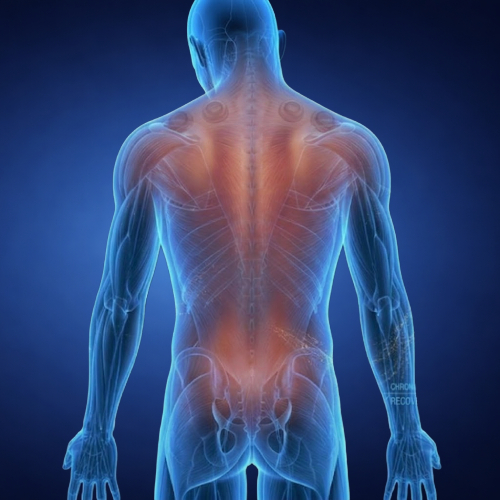

Neurotherapy is a natural, drug-free therapy that works by stimulating specific reflex points and nerve pathways in the body to support healing and improve function.

The therapy is based on the understanding that many health concerns may be linked to nerve imbalances, poor circulation, or blocked energy pathways.

By applying targeted stimulation, it aims to:

Activate natural healing responses

Improve nerve function

Support better blood flow

Restore internal balance

Enhances Nerve Function

Directly supports the proper and healthy functioning of nerve pathways.